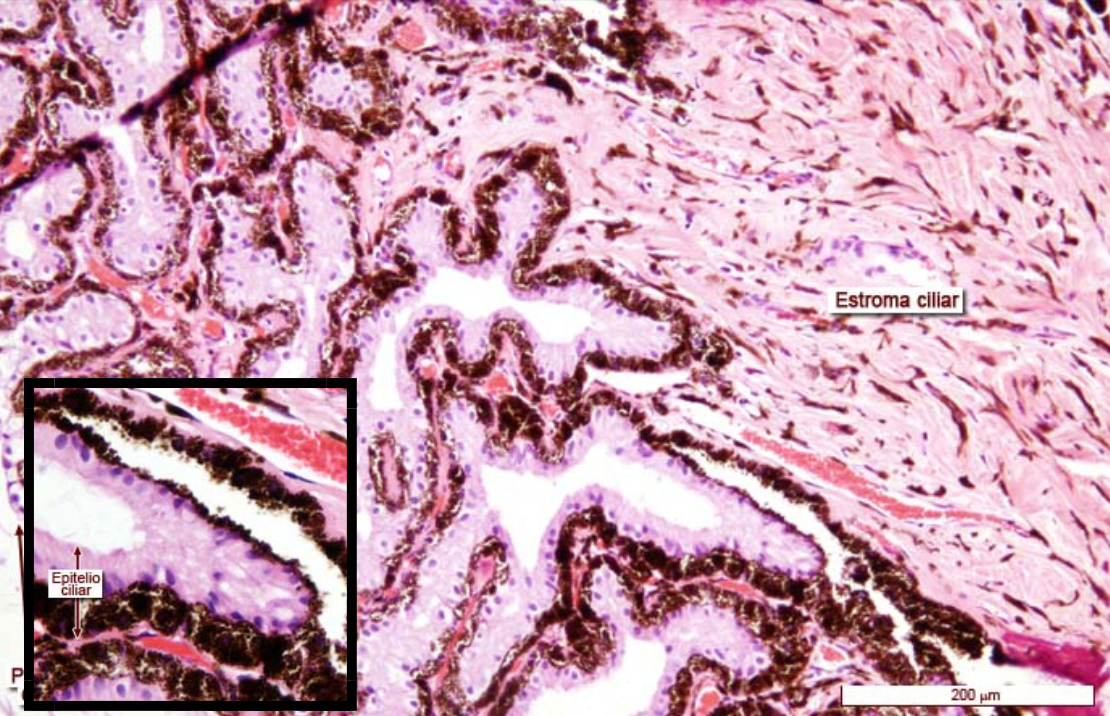

Componentes del cuerpo ciliar

A

Engrosamiento de la porción anterior de la túnica vascular entre iris y coroides

ESTROMA

Capa externa de músculo liso - músculo ciliar (acomoda al cristalino)

* Porción medial o longitudinal

* Porción radial u oblicua: visión lejana

* Porción circular o esfinterniana: visión cercana

Procesos ciliares: Evaginaciones del cuerpo ciliar.

Hay dispersas fibras elásticas y macrófagos, con gránulos de pigmento de melanina.

Región vascular interna

CAPA EPITELIAL Células columnares

Reviste la superficie interna del cuerpo ciliar

Capa pigmentada: Capa interna

Capa no pigmentada: Capa externa